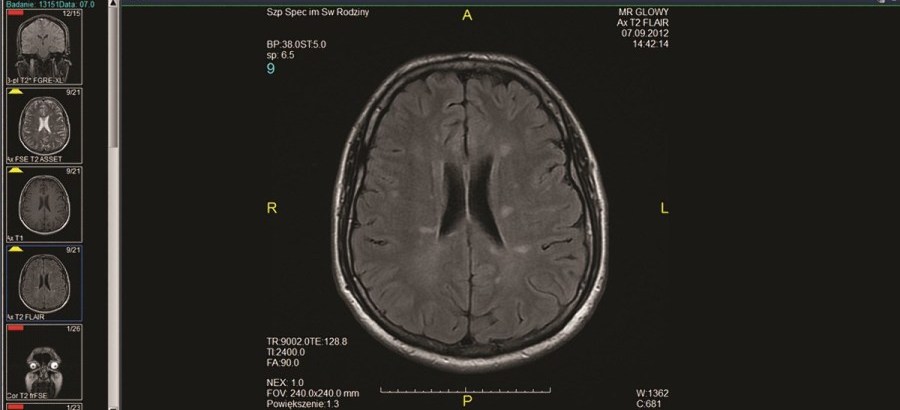

Lek. med. Iwona Rościszewska-Żukowska z Oddziału Neurologii z Udarowym Szpitala Specjalistycznego im. Św. Rodziny w Rudnej Małej